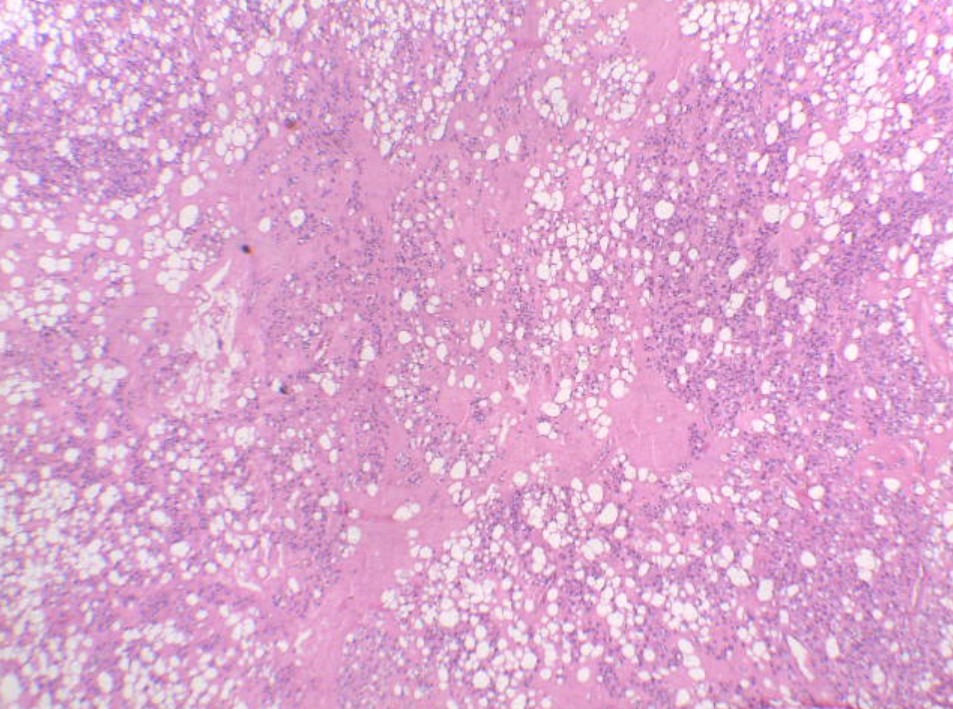

Mujer de 45 años con tumor en muslo derecho de lento crecimiento. Se realizó resección amplia de la lesión.

Lipoma condroide

Khin Thway, Rashpal Singh, Cyril Fisher. Chondroid lipoma: an update and review. Annals of Diagnostic Pathology 20112;16:230